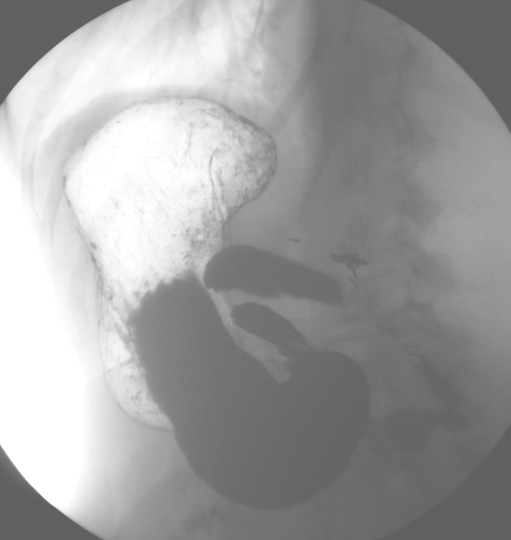

Identify the parts of the Stomach . Click the image for labeling.